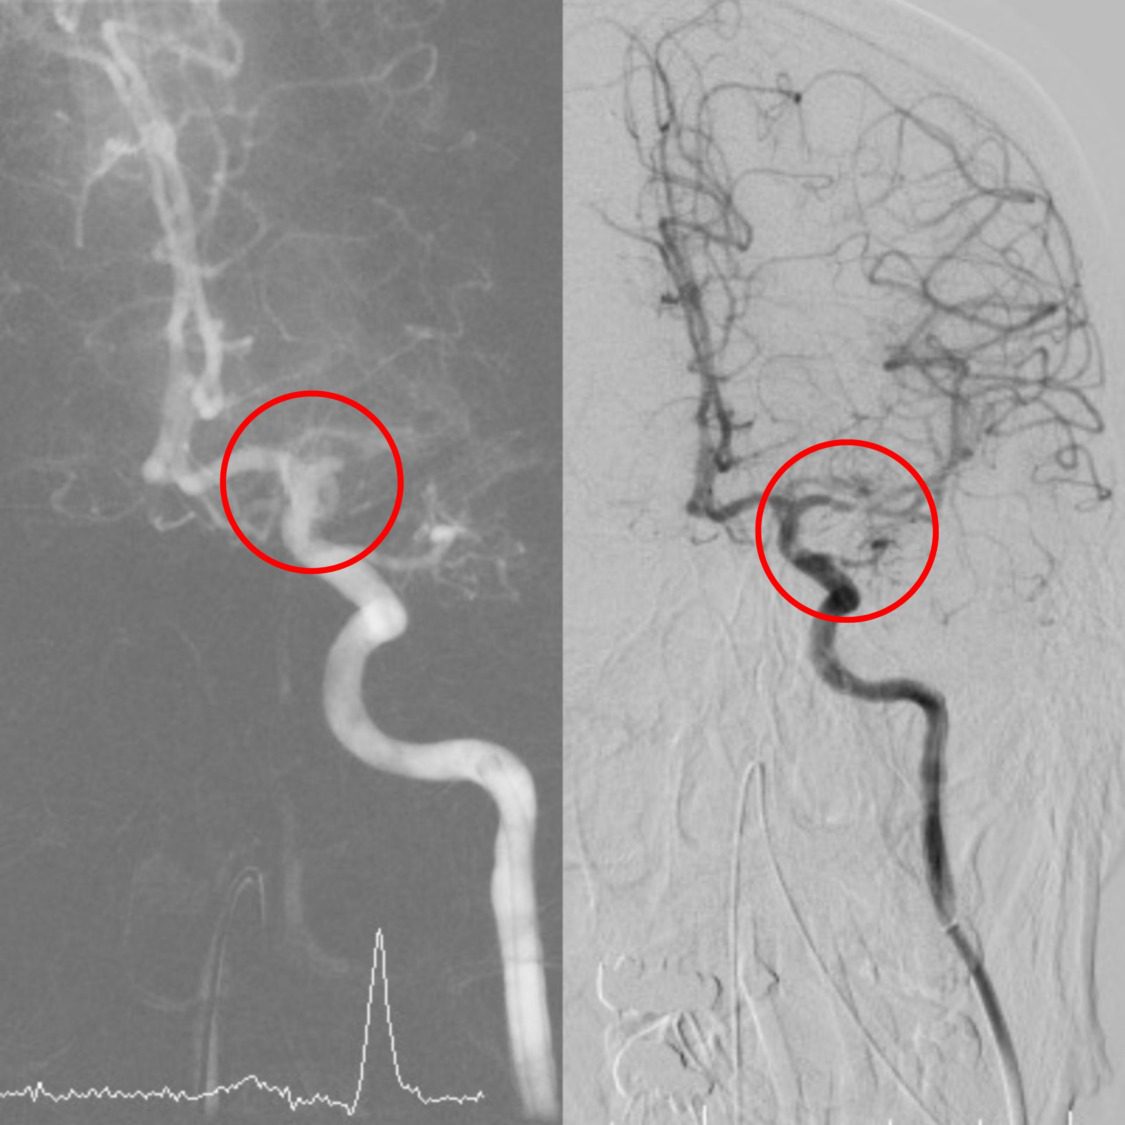

強化急重症醫療 小港醫院取栓團隊黃金時間搶救腦中風。〈圖/記者翻攝〉

林子超醫師接著說,顱內動脈取栓手術是已經逐漸普及的急性腦導管治療,醫師會從病人鼠蹊部的股動脈進行穿刺,藉由不同的導管組合,將抽吸導管或支架,從下肢動脈逆行到血栓塞住的顱內血管處,將血栓藉由支架取出或負壓吸出,相較於以往的血栓溶解劑治療及保守藥物治療,大血管梗塞的病患在接受顱內動脈取栓手術後,能獲得更積極的治療效果以及更好的預後。

2023年11月起,動脈取栓術給付條件也從中風後8小時延長至24小時內,其優點包括(1)在大血管梗塞的中風,提供給病患更積極的治療效果;(2)相較於血栓溶解劑治療,可治療病情更嚴重、送達急診時間更久的中風病患;(3)在執行手術過程中,可直接探查病患血管狀況,並發現其他隱藏的血管性病灶,如血管壁剝離、血管瘤或動靜脈畸形等。